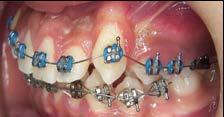

Tratamiento de caninos retenidos superiores en paciente en crecimiento con clase II división 2. Reporte de caso clínico

Los caninos retenidos constituyen una alteración eruptiva frecuente, con mayor prevalencia en la arcada superior. Su etiología es multifactorial y puede interferir con el trayecto normal de erupción, comprometiendo la oclusión y la estética.

Objetivo: Corregir una maloclusión Clase II división 2 mediante tratamiento ortodóntico en un paciente en crecimiento con ambos caninos superiores retenidos. Metodología: Se presenta el caso de un paciente masculino de 12 años, en dentición permanente, con perfil convexo, patrón dolicofacial y Clase II esquelética. Se realizó tratamiento ortodóntico sin extracciones. Para la tracción y alineación de los caninos retenidos se emplearon resortes abiertos (open coil springs) para la creación de espacio. Resultados: